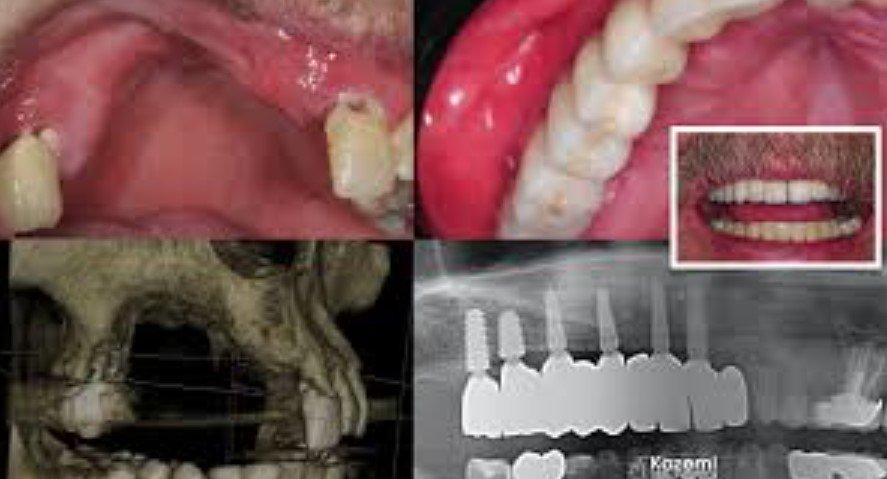

In more complex cases, a periodontist or oral and maxillofacial surgeon may order 3D imaging to evaluate the amount and shape of remaining bone before recommending surgery, grafting, or implants.

7) Dental Implants After Bone Regeneration

If bone loss happened because a tooth was missing, a dental implant may be the long-term replacement after the site is rebuilt. Cleveland Clinic notes that when there is not enough bone for immediate implant placement, bone grafting may be needed first and healing may take months before the implant is placed.

Implants can help restore chewing function and may help maintain bone by restoring stimulation to the jaw.